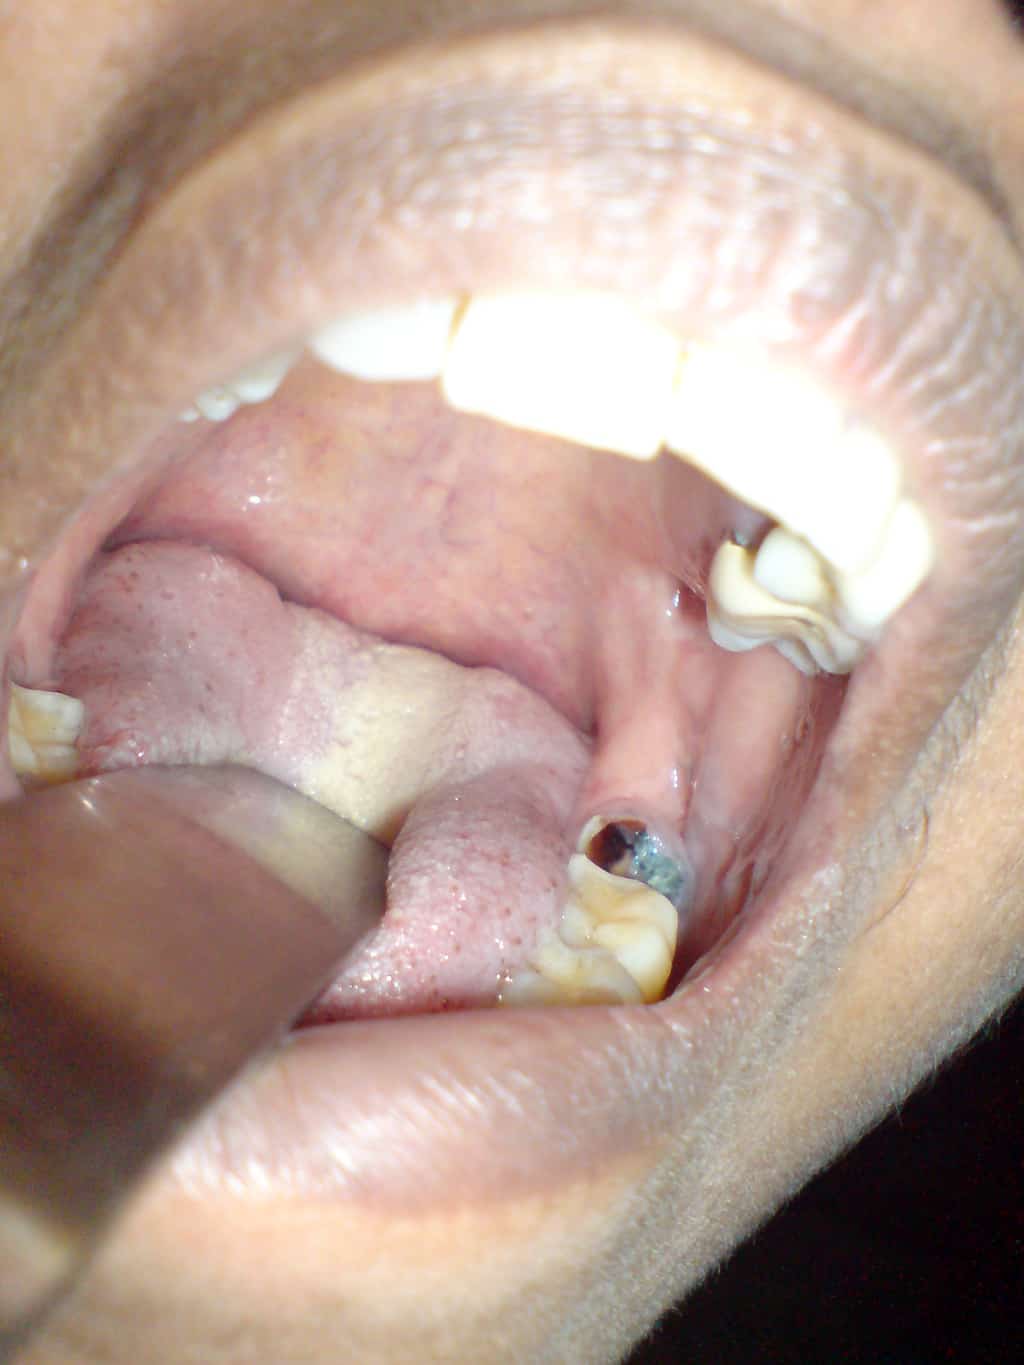

Tooth Decay: Dental Caries

A tooth cavity is the gradual breakdown of the tooth structure due to microbial growth. Erosion of the outer lining of the tooth (enamel) is followed by the destruction of the inner layer (dentin). A tooth cavity occurs as a result of a combination of factors, food particles get trapped on and between the teeth after eating and along with mucus, dead epithelial cells (from the mouth lining) and bacteria, a thin soft film, known as plaque coats the teeth. This provides the ideal medium for oral bacteria to feed upon food debris. Bacteria like streptococci and related groups, break down food particles and produce lactic acid as a byproduct. It is this lactic acid that is responsible for eroding tooth enamel and causing tooth cavities. Left untreated, the lactic acid will continue to erode the enamel and dentin and cause irritation of the nerve which is experienced as a toothache.

Diagnosis can be made simply by a using a dental probe to detect sensitivity at affected areas. A dental X-ray will provide further information on the severity of the cavity as well as any other considerations before commencing treatment.

Treatment: The area is filled with a restorative composite material (filling) and in severe cases, removal of the affected tooth may be necessary (extraction).